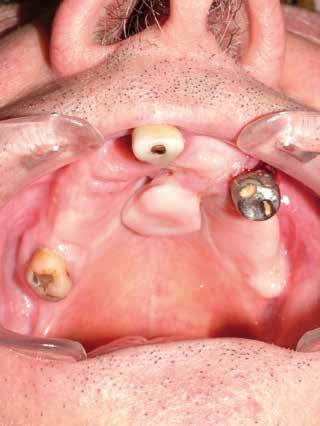

Deve prevedere sia l’osservazione sia la palpazione di tutte le mucose orali, partendo da labbra, lingua, guance, per arrivare alla valutazione del tessuto gengivale dei fornici, del palato e la gengiva aderente. Se ne devono valutare colore (fig. 11 ittero mucoso), fragilità, consistenza e presenza di ulcere o tumefazioni.

L’esame clinico rappresenta sicuramente la fase di analisi più complessa in quanto i parametri da valutare sono molti e possono interessare tutte le specialità odontoiatriche. Sono da valutare lo stato di salute della dentatura residua, la presenza o meno di manufatti protesici, il rapporto intermascellare,

lo stato di igiene orale, la condizione dei tessuti parodontali, le abrasioni dello smalto che ci indirizzino verso la diagnosi di parafunzioni come il bruxismo, la limitazione nell’apertura della bocca o la presenza di deviazioni per disordini temporo-mandibolari. (Figg. 16-21)

FIG. 17 FIG. 16 FIG. 19 FIG. 18 FIGG. 16-21: Valutazione FIG. 21 FIG. 20